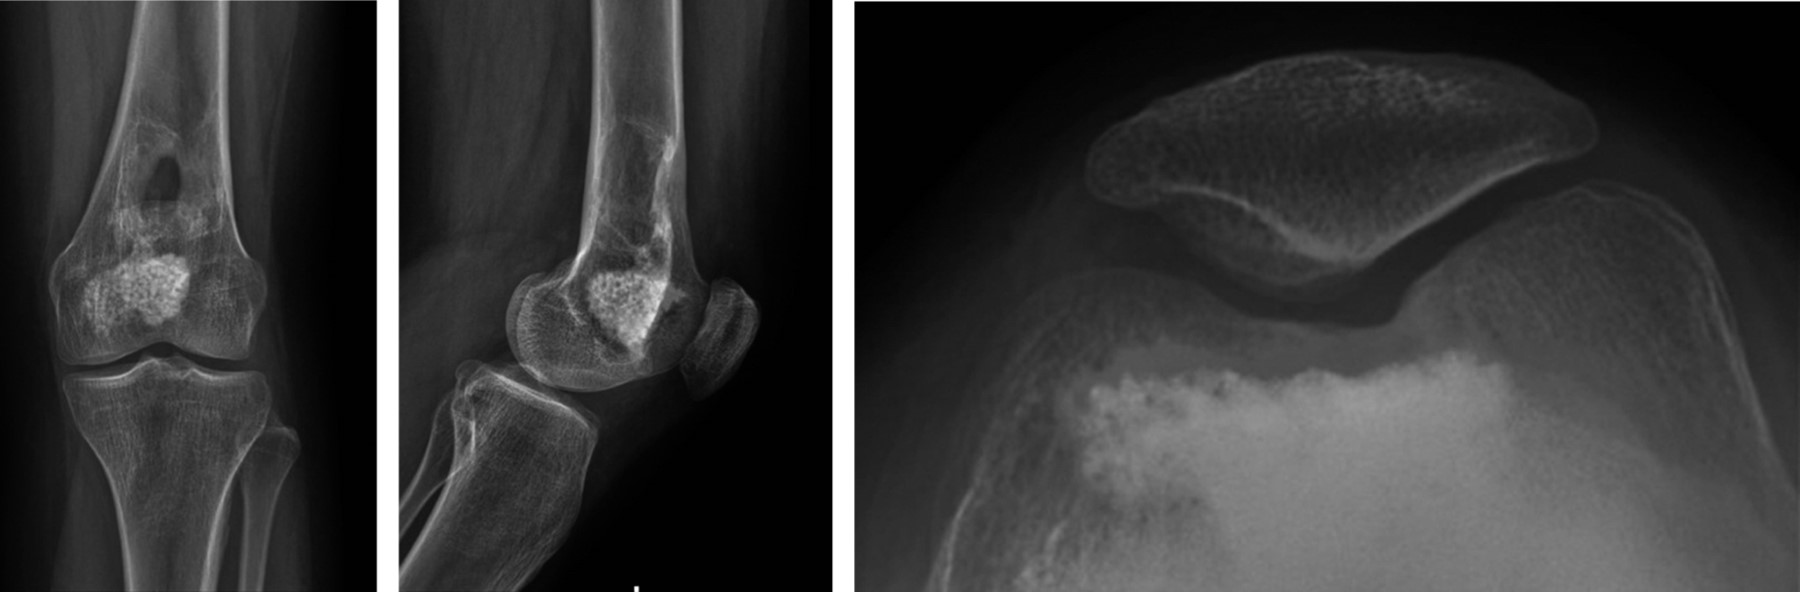

Durante el seguimiento radiológico y clínico estricto, se realizó un control inicial al mes postoperatorio, seguido de controles cada tres meses (Figura 4). Durante el último mes previo al control de los siete meses postoperatorios, la paciente presentó dolor constante afebril y sensación de calor local, sin otros signos de infección. Debido a estos síntomas, se solicitó una RMN de control con contraste, ésta reveló una pequeña lesión endomedular en la metáfisis distal de fémur, sugestiva de un foco de recidiva (Figura 5). Ante este hallazgo, se decidió una nueva intervención en la cual se realizó un segundo curetaje con biopsia, confirmando el diagnóstico de recidiva de condroblastoma. En esta intervención, no se aplicó injerto adicional y se optó por una resección intralesional completa sin adyuvancia.

La paciente se mantuvo, posterior a la segunda intervención, sin nuevos síntomas, con controles radiológicos periódicos, sin nuevos hallazgos. Consultó a los tres años postoperada por dolor anterior de rodilla, sin antecedente de trauma, describiéndose una rodilla estable, sin aumento de volumen ni de temperatura local, con dolor ubicado en relación a la articulación patelofemoral. Se tomaron imágenes radiográficas y TAC de rodilla izquierda en las que se muestra la presencia de una lesión quística postoperatoria en región metafisaria, no sugerente de recidiva (Figuras 6 y 7). Este cuadro se manejó de manera efectiva con fisioterapia enfocada en fortalecimiento muscular y propiocepción.

Por última vez, consulta a los 20 años, cinco años posterior a la primera cirugía, por molestias en relación a rodilla izquierda, específicamente en la articulación patelofemoral. Sin signos de alarma descritos. Se tomaron radiografías, sin evidencias de recidiva ni de complicaciones. Se observó un defecto óseo en la zona de recidiva, compatible con el curetaje realizado previamente (Figura 8).